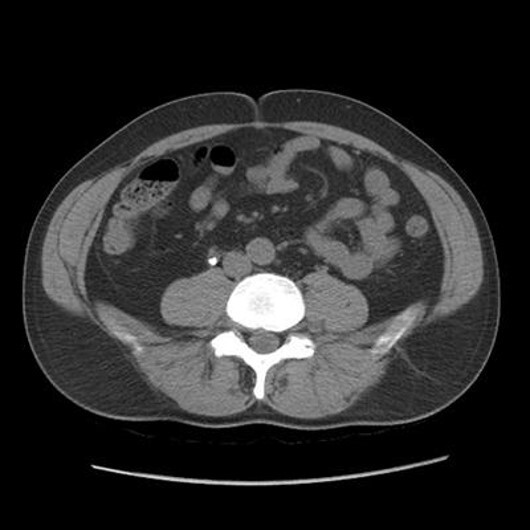

What pathology is seen here?

Polycystic Kidney Disease